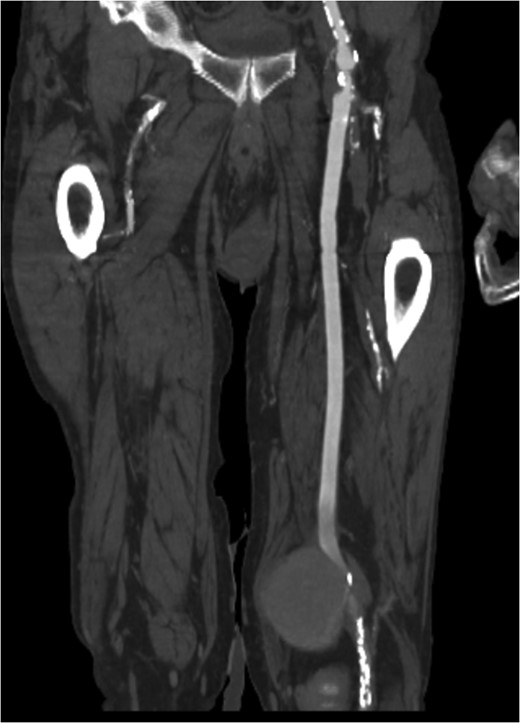

Pseudoaneurysm (PA) following vascular reconstruction is a complication of bypass surgery. Historically, the mainstay of treatment was an open repair; the surgical management consisted of resection of the initial graft with reimplantation of a new bypass either into the original arteriotomy or to a more distal target. Placement of a stent graft to exclude the PA is a viable option. We present a case of an 85-year-old man with prior history of polytetrafluoroethylene femoral–popliteal bypass now with an 8 × 5.6 cm PA of the distal anastomosis site treated with endovascular placement of a Viabahn stent.

Pseudoaneurysm (PA) formation has been described in the literature as a delayed presentation in surgically revascularized patients. Given the rising number of reconstructive vascular procedures, the increase in anastomotic PA cases is expected [1]. Potential degeneration of biosynthetic grafts with aneurysm formation is a well-known problem with a reported incidence of up to 7% [2]. Implantation of a stent graft for treatment of a PA is a valuable treatment option in native arteries, as well as bypass grafts, as reported by Magnetti et al. [2]. In high-surgical-risk patients, the placement of a stent graft provides a safe and effective option for the treatment of anastomotic PA. We present a case of an 85-year-old man with prior history of polytetrafluoroethylene (PTFE) femoral–popliteal bypass now with an 8 × 5.6 cm PA of the distal anastomosis site treated with endovascular placement of a Viabahn stent. Of note, the patient underwent open thrombectomy and patch angioplasty of the site 10 years prior. Proper written consent was obtained from the patient prior to the creation of this case report.

Coronal view of popliteal PS of distal anastomosis site of femoral–popliteal bypass.